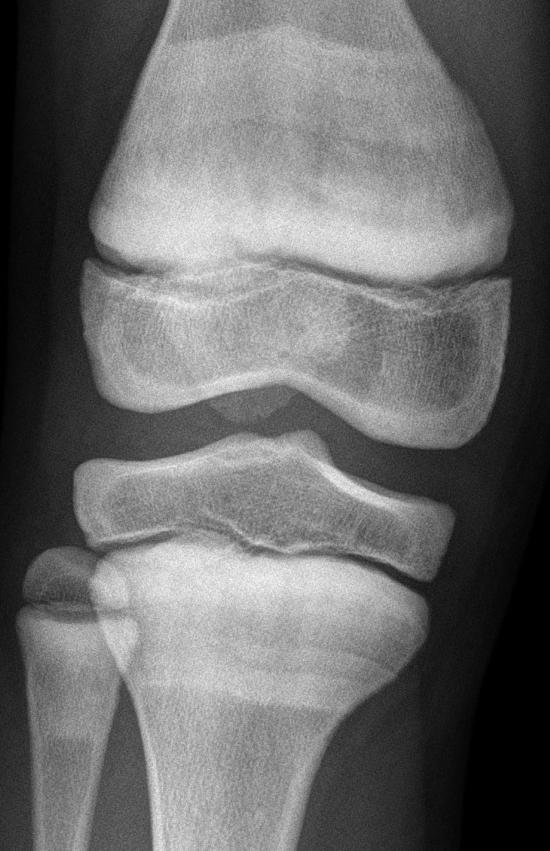

Een jongen met witte strepen op de röntgenfoto van zijn knie

Een 10-jarige jongen met de ziekte van Perthes komt bij de huisarts wegens pijn aan zijn rechter knie. De huisarts laat röntgenfoto’s maken. Hierop worden streepvormige botverdichtingen gezien. Wat is de oorzaak daarvan?